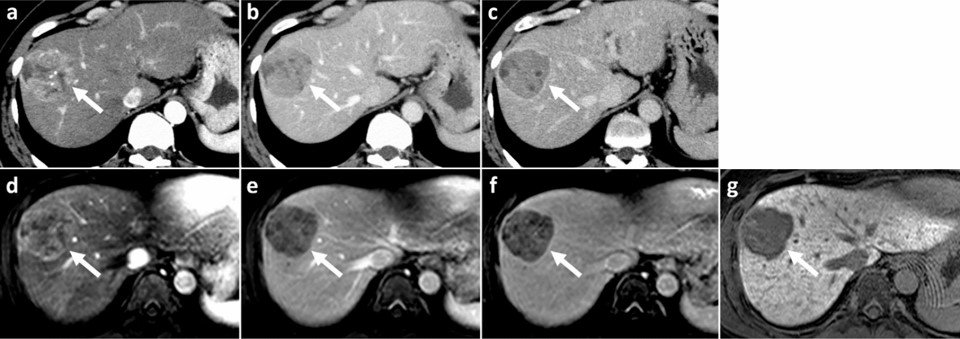

CT and MR images in a 37-year-old male with poorly-differentiated HCC with histological capsule. METAVIR score of the background liver was F3. In contrast-enhanced CT, a 49-mm observation shows (a) nonrim APHE on arterial phase and (b) nonperipheral washout with an enhancing capsule on equilibrium phase. In gadoxetic acid-enhanced MRI, a 48-mm observation shows (c) nonrim APHE on arterial phase, (d) nonperipheral washout on portal venous phase, and (e) TP hypointensity with suspicion of an enhancing capsule on transitional phase. Hepatobiliary phase image clearly shows (f) a nonenhancing capsule surrounding the observation.